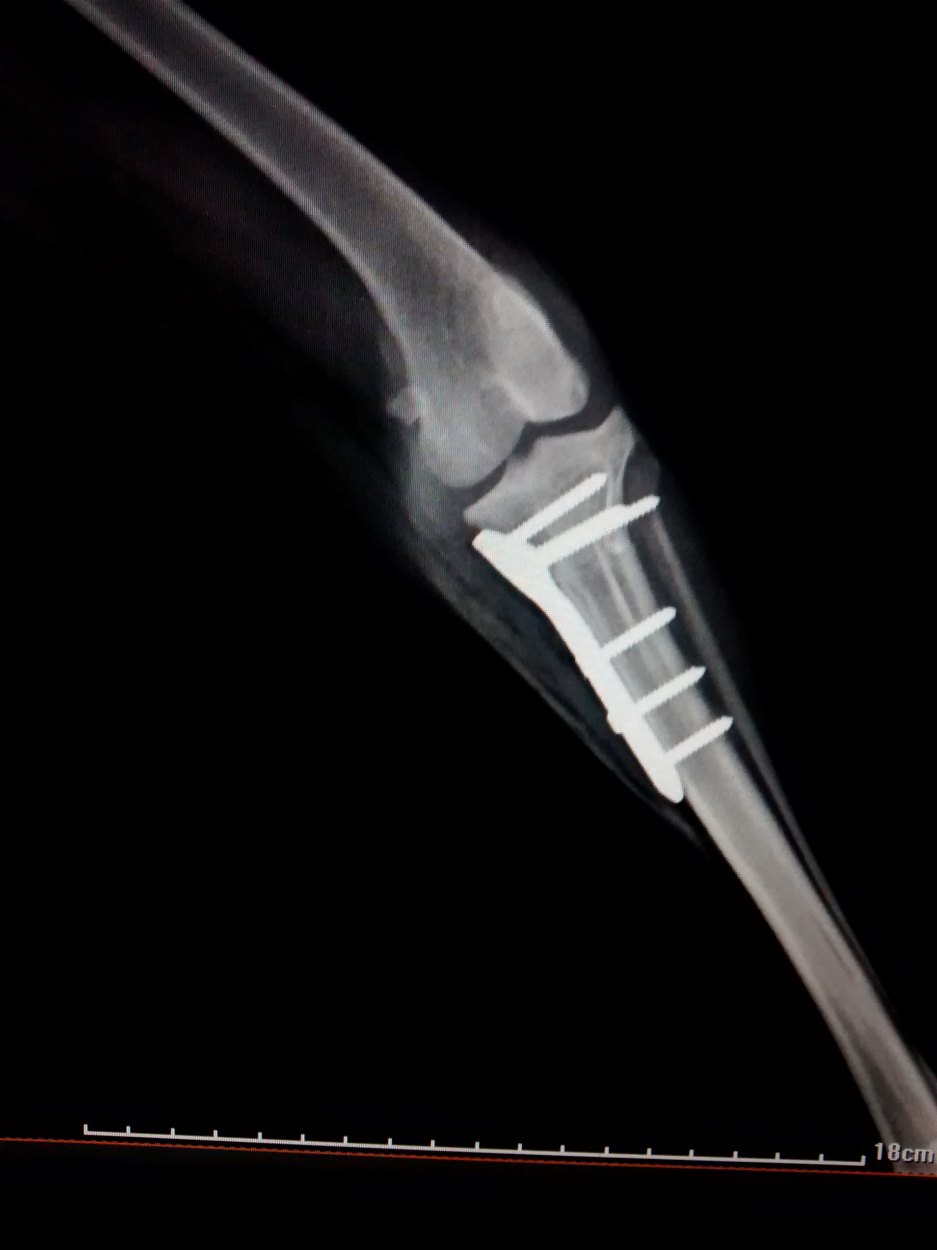

A Ruptura de ligamento cruzado cranial (RLCcr) é uma afecção muito comum nos cães, este caso refere-se a um cão macho mancando de forma aguda que ao exame foi feito o diagnostico de RLCcr. Optou-se por sua correção cirúrgica utilizando a ténica de TPLO, mundialmente conhecida pela sua alta eficácia.